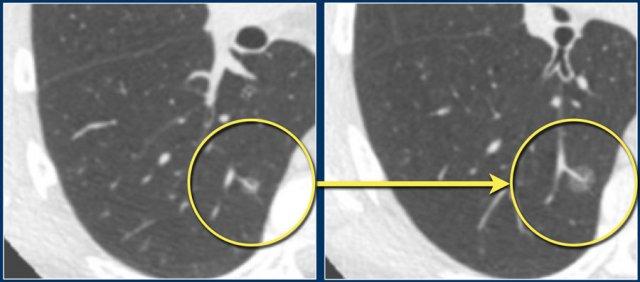

Các hình ảnh này cho thấy một nốt bán đặc kính mờ thuần túy ở thùy dưới phổi phải.

Tổn thương này cho thấy sự tăng trưởng trong khoảng thời gian hai năm và được xác nhận là ác tính sau khi phẫu thuật cắt bỏ.